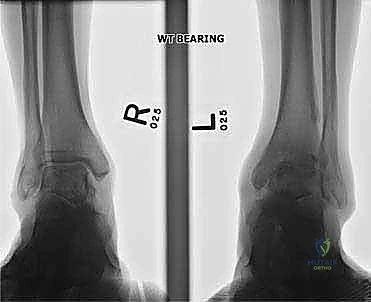

التصوير الطبي المتقدم (Medical Imaging)

لتأكيد التشخيص ووضع الخطة الجراحية، يتم الاعتماد على أحدث تقنيات التصوير:

- الأشعة السينية أثناء الوقوف (Weight-bearing X-rays): هي الفحص الذهبي والأهم. يجب أن تؤخذ الأشعة والمريض واقف لتحمل الوزن. تظهر الأشعة تضيق المسافة المفصلية (دليل على فقدان الغضروف)، وجود نتوءات عظمية، تصلب العظم، وأي انحراف في محور المفصل.

- التصوير المقطعي المحوسب (CT Scan): يطلبه الدكتور هطيف لتقييم جودة العظام (Bone stock)، تحديد حجم الأكياس العظمية، ورسم خريطة ثلاثية الأبعاد للتشوهات المعقدة قبل الجراحة.